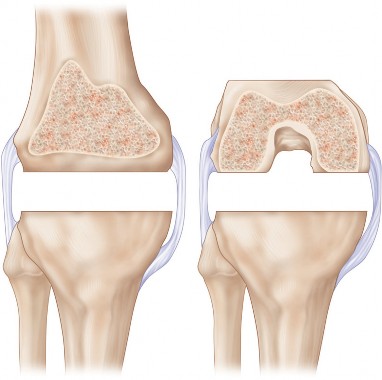

الانحراف التقوسي، المعروف أيضًا بـ "تقوس الساقين" أو "الركبة المقوسة"، هو حالة تتميز بوجود زاوية غير طبيعية في مفصل الركبة، حيث تتجه الركبة نحو الخارج بينما تتجه الكاحلين نحو الداخل عند الوقوف معًا. هذا يعني أن الساقين تبدوان مقوستين إلى الخارج، مما يضع ضغطًا مفرطًا على الجزء الداخلي (الإنسي) من مفصل الركبة.

في الركبة الطبيعية، يمر خط وزن الجسم بشكل متساوٍ تقريبًا عبر مركز المفصل. أما في الركبة التقوسية، فإن هذا الخط ينحرف نحو الجانب الإنسي، مما يؤدي إلى:

- زيادة الضغط على الغضروف الإنسي: يتسبب هذا الضغط المستمر في تآكل الغضروف في الجزء الداخلي من الركبة بشكل أسرع بكثير من الجزء الخارجي.

- تضييق المسافة المفصلية الإنسية: مع تآكل الغضروف، تقل المسافة بين عظم الفخذ وعظم الساق في الجانب الداخلي، مما يزيد من الاحتكاك والألم.

- تلف الأنسجة الرخوة: يمكن أن يؤثر الضغط غير المتوازن على الأربطة والأنسجة المحيطة، مما يزيد من عدم الاستقرار.

يُعد الانحراف التقوسي مشكلة شائعة وقد يكون خلقيًا (موجودًا منذ الولادة)، ولكنه غالبًا ما يتطور بمرور الوقت نتيجة لخشونة الركبة المتقدمة، حيث يؤدي التآكل غير المتساوي للغضروف إلى تفاقم التشوه. تصحيح هذا الانحراف هو جوهر جراحة استبدال مفصل الركبة التقوسي، وهو ما يتقنه الأستاذ الدكتور محمد هطيف لضمان استقرار المفصل وطول عمره.